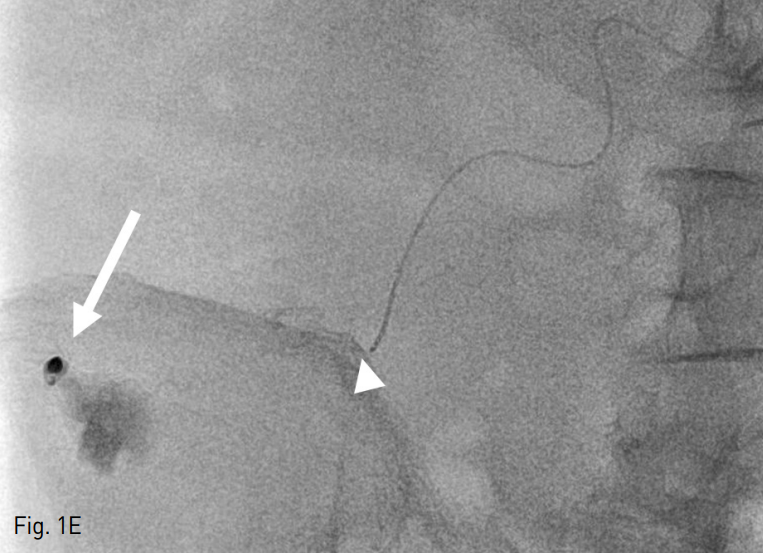

Fig. 1. A 75-year-old man with Jackson-Pratt catheter tract bleeding after radical excision of right kidney.

E. A superselective embolization of the bleeding focus (arrow) using 25% NBCA mixture with Lipiodol was success fully done while the tip of a microcatheter was wedged into a single vasa rectum (arrowhead) to avoid overflow of the liquid embolic agent.